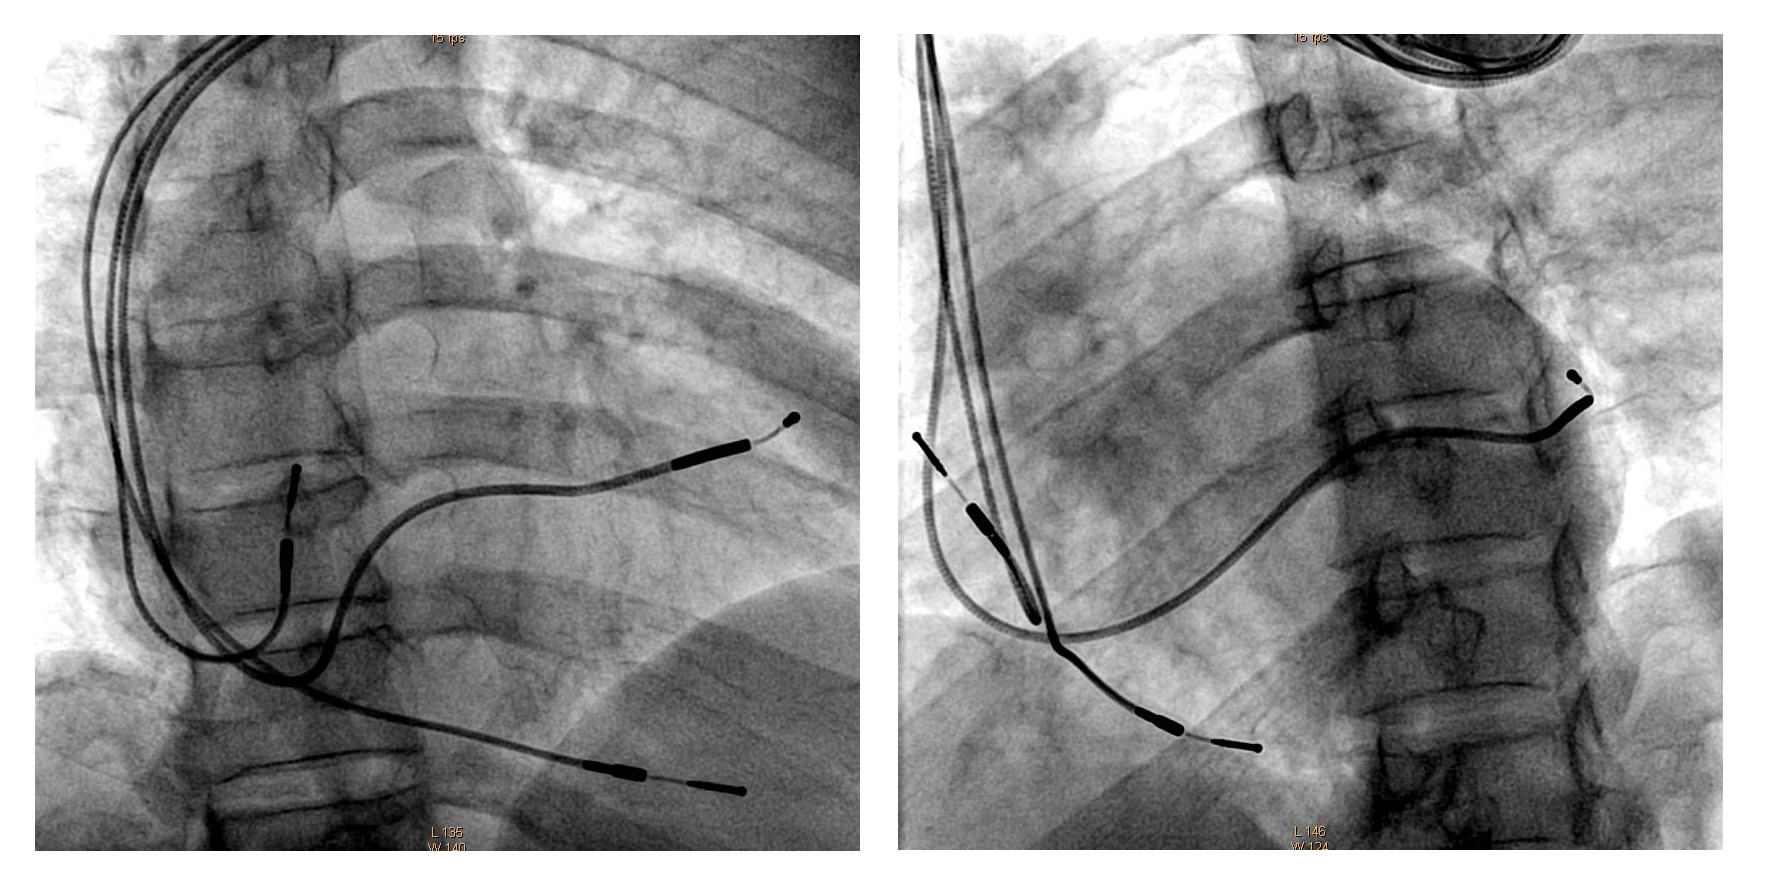

CRT implant

crt_views.jpg